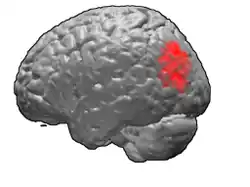

Brodmann area 39

Brodmann area 39, or BA39, is part of the parietal cortex in the human brain. BA39 encompasses the angular gyrus, lying near to the junction of temporal, occipital and parietal lobes.

This area is also known as angular area 39 (H). It corresponds to the angular gyrus surrounding the caudal tip of the superior temporal sulcus. It is bounded dorsally approximately by the intraparietal sulcus. In terms of its cytoarchitecture, it is bounded rostrally by the supramarginal area 40 (H), dorsally and caudally by the peristriate area 19, and ventrally by the occipitotemporal area 37 (H) (Brodmann-1909).